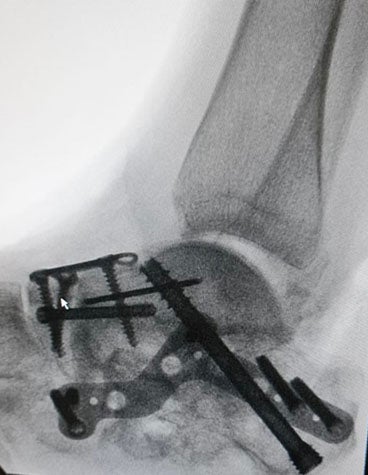

Image credit: Synergy3DMed

족관절 전치환술은 이 부문의 성장을 주도하는 주요 요인입니다. 3D 계획 및 환자별 맞춤형 의료기기와 같은 첨단 기술이 이러한 변화를 가능하게 하여 복잡한 해부학적 구조에 대한 더 나은 인사이트와 솔루션을 제공합니다.

절골술도 유망한 증가세를 보이고 있으며, Distal Tibia의 돔형태의 절골술과 같은 흥미로운 사례도 생겨났습니다. 이러한 발목 절골술의 인기 증가에 기여하고 있는 Materialise 및 Synergy3DMed와 같은 회사는 외과의가 정확하고 대칭적인 결과를 얻을 수 있도록 PSI를 지원합니다.